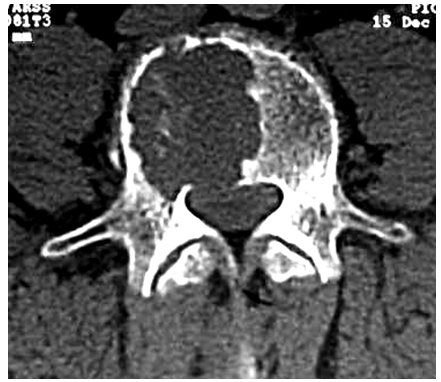

Ciment cem i 42,5 n ce pmes cp2 nf et adjuvants pour réaliser des coulis d'injection de dosage 1 sac de ciment de 25 kg pour une poche d'adjuvants ; En france, on peut injecter du ciment (en fait une sorte de résine) dans des vertèbres fragilisées pour les renforcer, mais pas directement dans les disques de il peut en effet y avoir des fuites de ciment et des complications au niveau des nerfs et des artères ainsi qu'un risque vital en cas d'hémorragie. C'est en 2011 qu'elle a été arrêtée pour pratique illégale de la médecine, à la suite d'une plainte d'une patiente gravement blessée.

L'injection de ciment osseux (vertébroplastie) est sûre, efficace et à un coût acceptable pour les patients souffrant de fractures vertébrales ostéoporotiques aiguës. Le brochage des dalles avec injection de coulis de ciment. Ce texte a été rédigé dans le cadre d'une recherche plus vaste menée en collaboration avec la chaire de gestion du secteur de l'énergie de hec montréal, pour le compte du.

.localisations vertébroplastie injection de ciment acrylique dans le corps vertébral vert moins autant de vertébroplasties faites •de nombreuses études faites dans le depuis 2005 10 patients par an •environ 1500 vertèbres traitées dans le service.